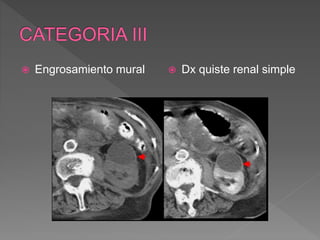

 Engrosamiento mural  Dx quiste renal simple

 Engrosamiento mural

quistico.

› Engrosamiento uniforme o

levemente nodular de la

pared

 Riesgo de malignidad 50%

 Requiere control quirúrgico

 Variabilidad interobservador

 Hallazgos imagenologicos:

› Pared y septos numerosos,

gruesos >1cm, regulares o

no cn realce evidente

› Calcificaciones groseras o

irregulares parietales o de

los tabiques.